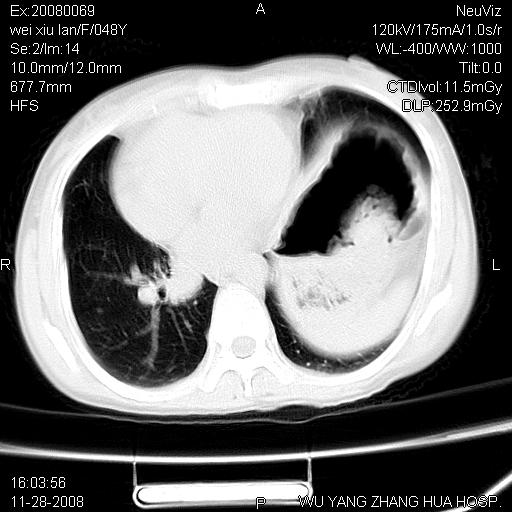

标题: CT16847:女,48岁,咳嗽,发热两日,平常偶有上腹部不适。 [打印本页]

标题: CT16847:女,48岁,咳嗽,发热两日,平常偶有上腹部不适。

能否考虑食管裂孔疝?请老师们多多指教。

这个是左侧膈膨升伴不完全性胃翻转,手术将松弛的左横膈膜折叠缝合即解决问题。

支持左侧膈疝,心脏受压右移.

左下肺不张、膈膨升,胸腔胃

胃、脾脏及部分肠管明显升高,并压迫心脏移位,

首先考虑:左侧膈疝。

左侧胸腔内见胃肠及脾脏影

支持膈疝

左膈顶及肋膈角均上移,膈面光滑,考虑左膈肌麻痹